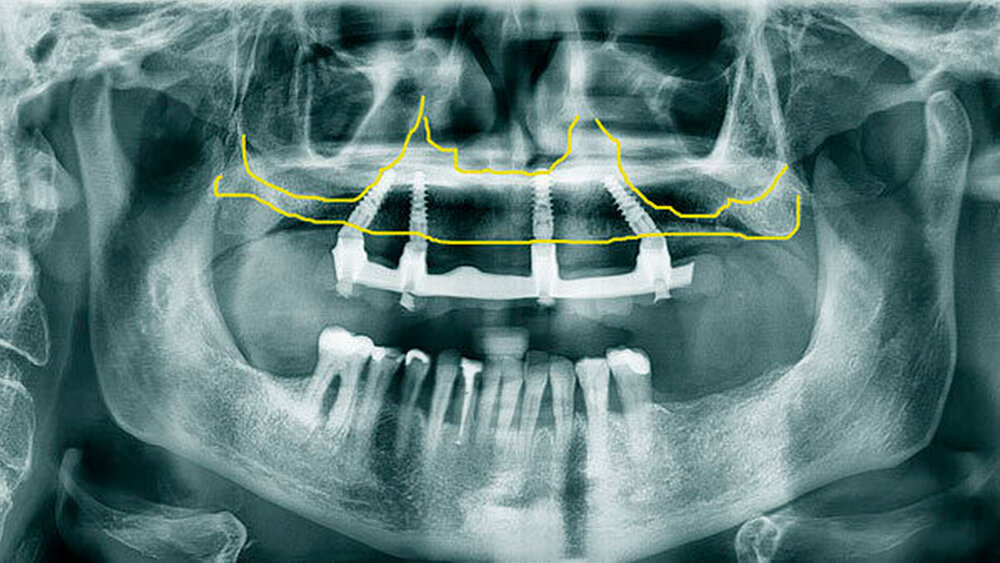

Das All-on-4 Konzept auf Zygoma-Implantaten

Eine erhebliche Erweiterung der Indikation des All-on-4 Konzeptes konnte durch den Einsatz von Zygoma-Implantaten erzielt werden. Zygoma-Implantate werden im Os zygomaticum verankert und erreichen auch in Situationen mit starker Kieferkammatrophie eine hohe Primärstabilität. Herkömmliche augmentative Verfahren können so vermieden werden. Zygoma-Implantate wurden zunächst bei Patienten mit besonderen Dysplasien im Kieferbereich und bei Tumorpatienten nach Resektion von Kieferanteilen eingesetzt. Balshi war einer der ersten Kliniker, der mit speziell gestalteten Implantaten entsprechende Fälle versorgte. Die Übertragung des All-on-4 Konzeptes auf Zygoma-Implantat-getragene Versorgungen ist insbesondere mit dem Namen Malavez verbunden, die sich sehr um diese Technik verdient gemacht hat. Dieses Konzept auf Zygoma-Implantaten wird angewendet in Fällen mit ausgeprägter Kieferkammatrophie im Oberkiefer (Abbildung 4a). Die Zygoma-Implantate werden in aller Regel in ITN inseriert. Lediglich ein externer Sinuslift ist als augmentative Maßnahme notwendig (Abbildungen 4b und c). Durch dieses Vorgehen können aufwändige augmentative Verfahren umgangen werden. Die prothetische Versorgung der Zygoma-Implantate entspricht dem Vorgehen wie beim All-on-4 Konzept und erfolgt einen Tag postoperativ. Erreicht wird, wie beim ursprünglichen All-on-4 Konzept, eine festsitzende Sofortversorgung (Abbildungen 3 und 4d).

Während die Behandlungszeit bei komplexen Augmentationen ein Jahr und mehr betragen kann, ist bei Verwendung von Zygoma-Implantaten eine festsitzende Sofortversorgung möglich. Eine Kombination von konventionellen Implantaten bei lokal ausreichendem Knochenangebot mit Zygoma-Implantaten bei lokal unzureichendem Knochenangebot ist möglich.